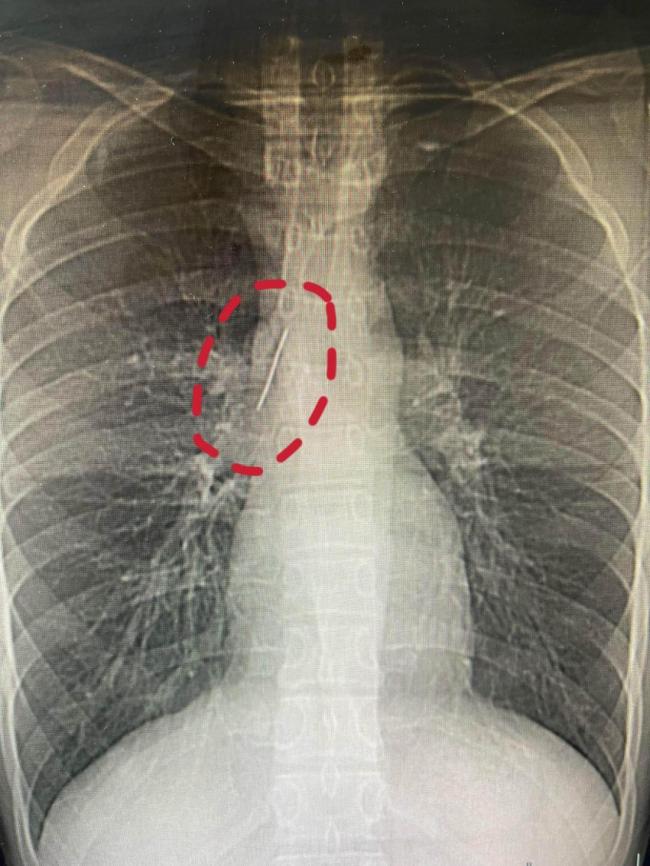

17岁的小陆在一次参军体检中意外发现了一个隐藏多年的秘密:一根长达5厘米的锈迹斑斑的缝衣针藏在他的胸腔里。这根针紧贴大血管、刺入肺组织,多年来竟毫无痛感,未引发感染或气胸,堪称医学奇迹。小陆对这根针的来源一无所知,成年后完全没有相关记忆

小陆老家在安徽,从小跟着父母在嘉兴做水果生意,目前在富阳一所职高读书,身体素质一向不错。不久前,他满怀期待参加征兵体检,没想到胸片结果显示他的胸腔内有一处明显的金属高密度影,形态细长,像一根针。进一步CT检查确认,异物是一根金属针,斜插在肺组织内,针尖紧紧贴着胸主动脉和上腔静脉等重要血管,稍有位移就可能刺破血管引发致命大出血。

面对这一结果,小陆和家人非常震惊。针体已刺入肺实质,却没有造成气胸、血胸,也没有感染发炎。小陆平时跑跳、运动都毫无异常,从未出现胸闷、胸痛、咳血等症状。小陆父母反复回忆,终于想起十多年前小陆曾长时间哭闹不止,当时没找到原因,大概率就是那次意外导致针被扎入体内。